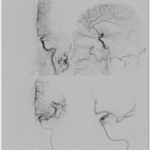

Brain Arteriovenous Malformation (AVM) Embolization

An Arteriovenous malformation or AVM is an abnormal connection between arteries and veins, bypassing the capillary system. This vascular anomaly is widely known because of its occurrence in the central nervous system, but can appear in any location. Although many AVMs are asymptomatic, AVMs in the brain can cause intense headache, intracranial bleeding, and/or lead to other serious medical problems, such as seizures. Vascular malformations can be treated endovascularly with embolization using liquid embolics, such as Onyx and n-BCA, by open surgery, or by gamma knife radiosurgery. Sometimes these lesions are treated by a combination of the above mentioned therapies.

Dural Arteriovenous Fistula (AVF) Embolization

A duralarteriovenous fistula (DAVF) is an abnormal direct connection (fistula) between a meningealartery and a meningeal vein or dural venous sinus. Like other vascular malformations, a dural AVF can be treated endovascularlywith embolization using liquid embolics, such as Onyx and n-BCA, by open surgery, or by gamma knife radiosurgery. Sometimes these lesions are treated by a combination of the above mentioned therapies.